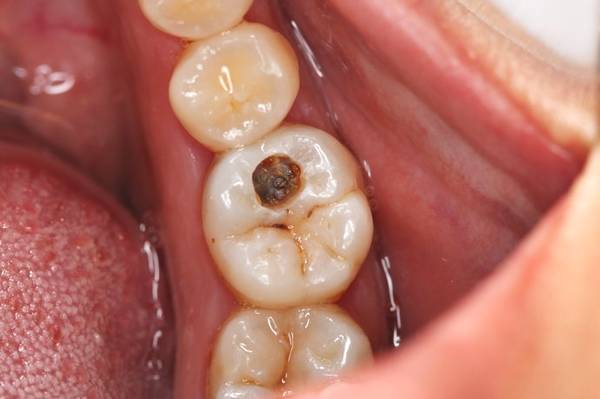

中龋

病变进展到牙本质,有明显蛀牙洞,受外界的冷、热、酸、甜等刺激会出现疼痛反应,当刺激源去除后疼痛立即消失。

治疗方法:树脂充填(补牙)

深龋

伤到牙本质深层,蛀牙洞大而深,受到外界刺激时疼痛加剧,但刺激消失后疼痛会停止。

治疗方式:护髓、充填